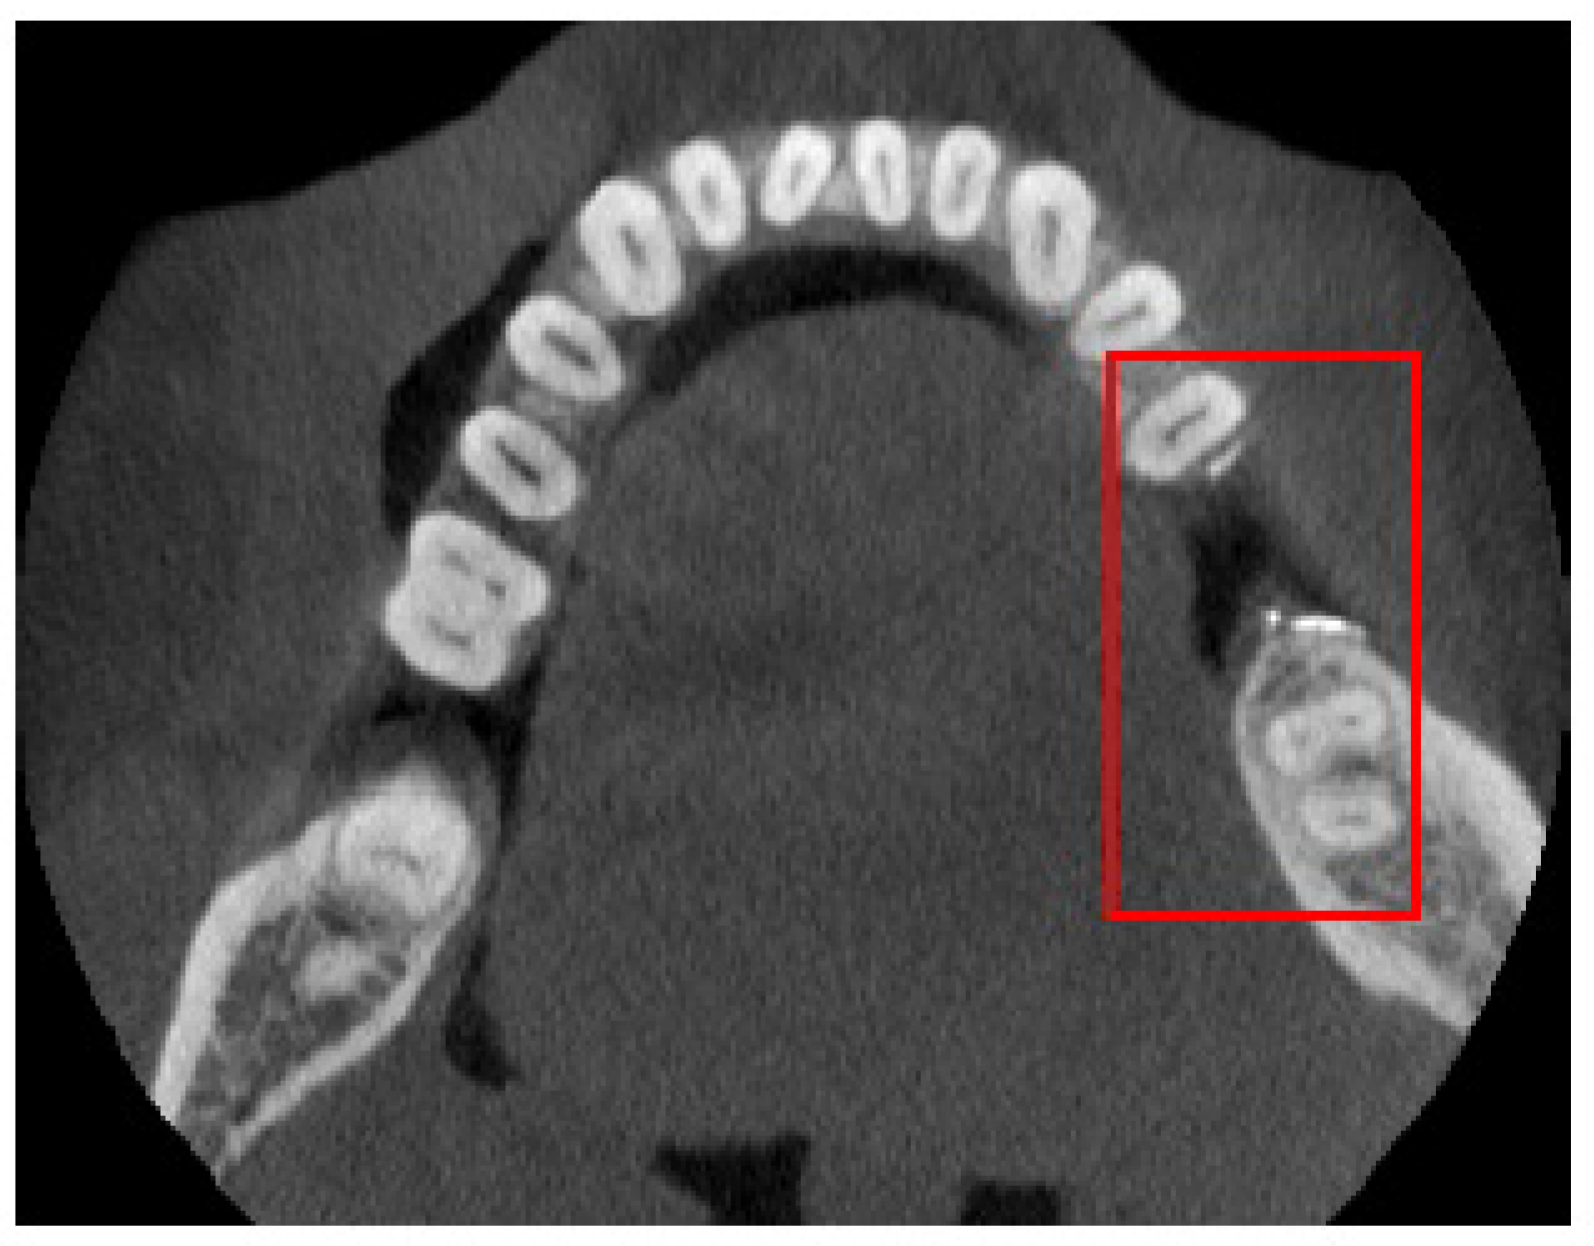

3. Numerical Results

| ROI | Region of Interest |